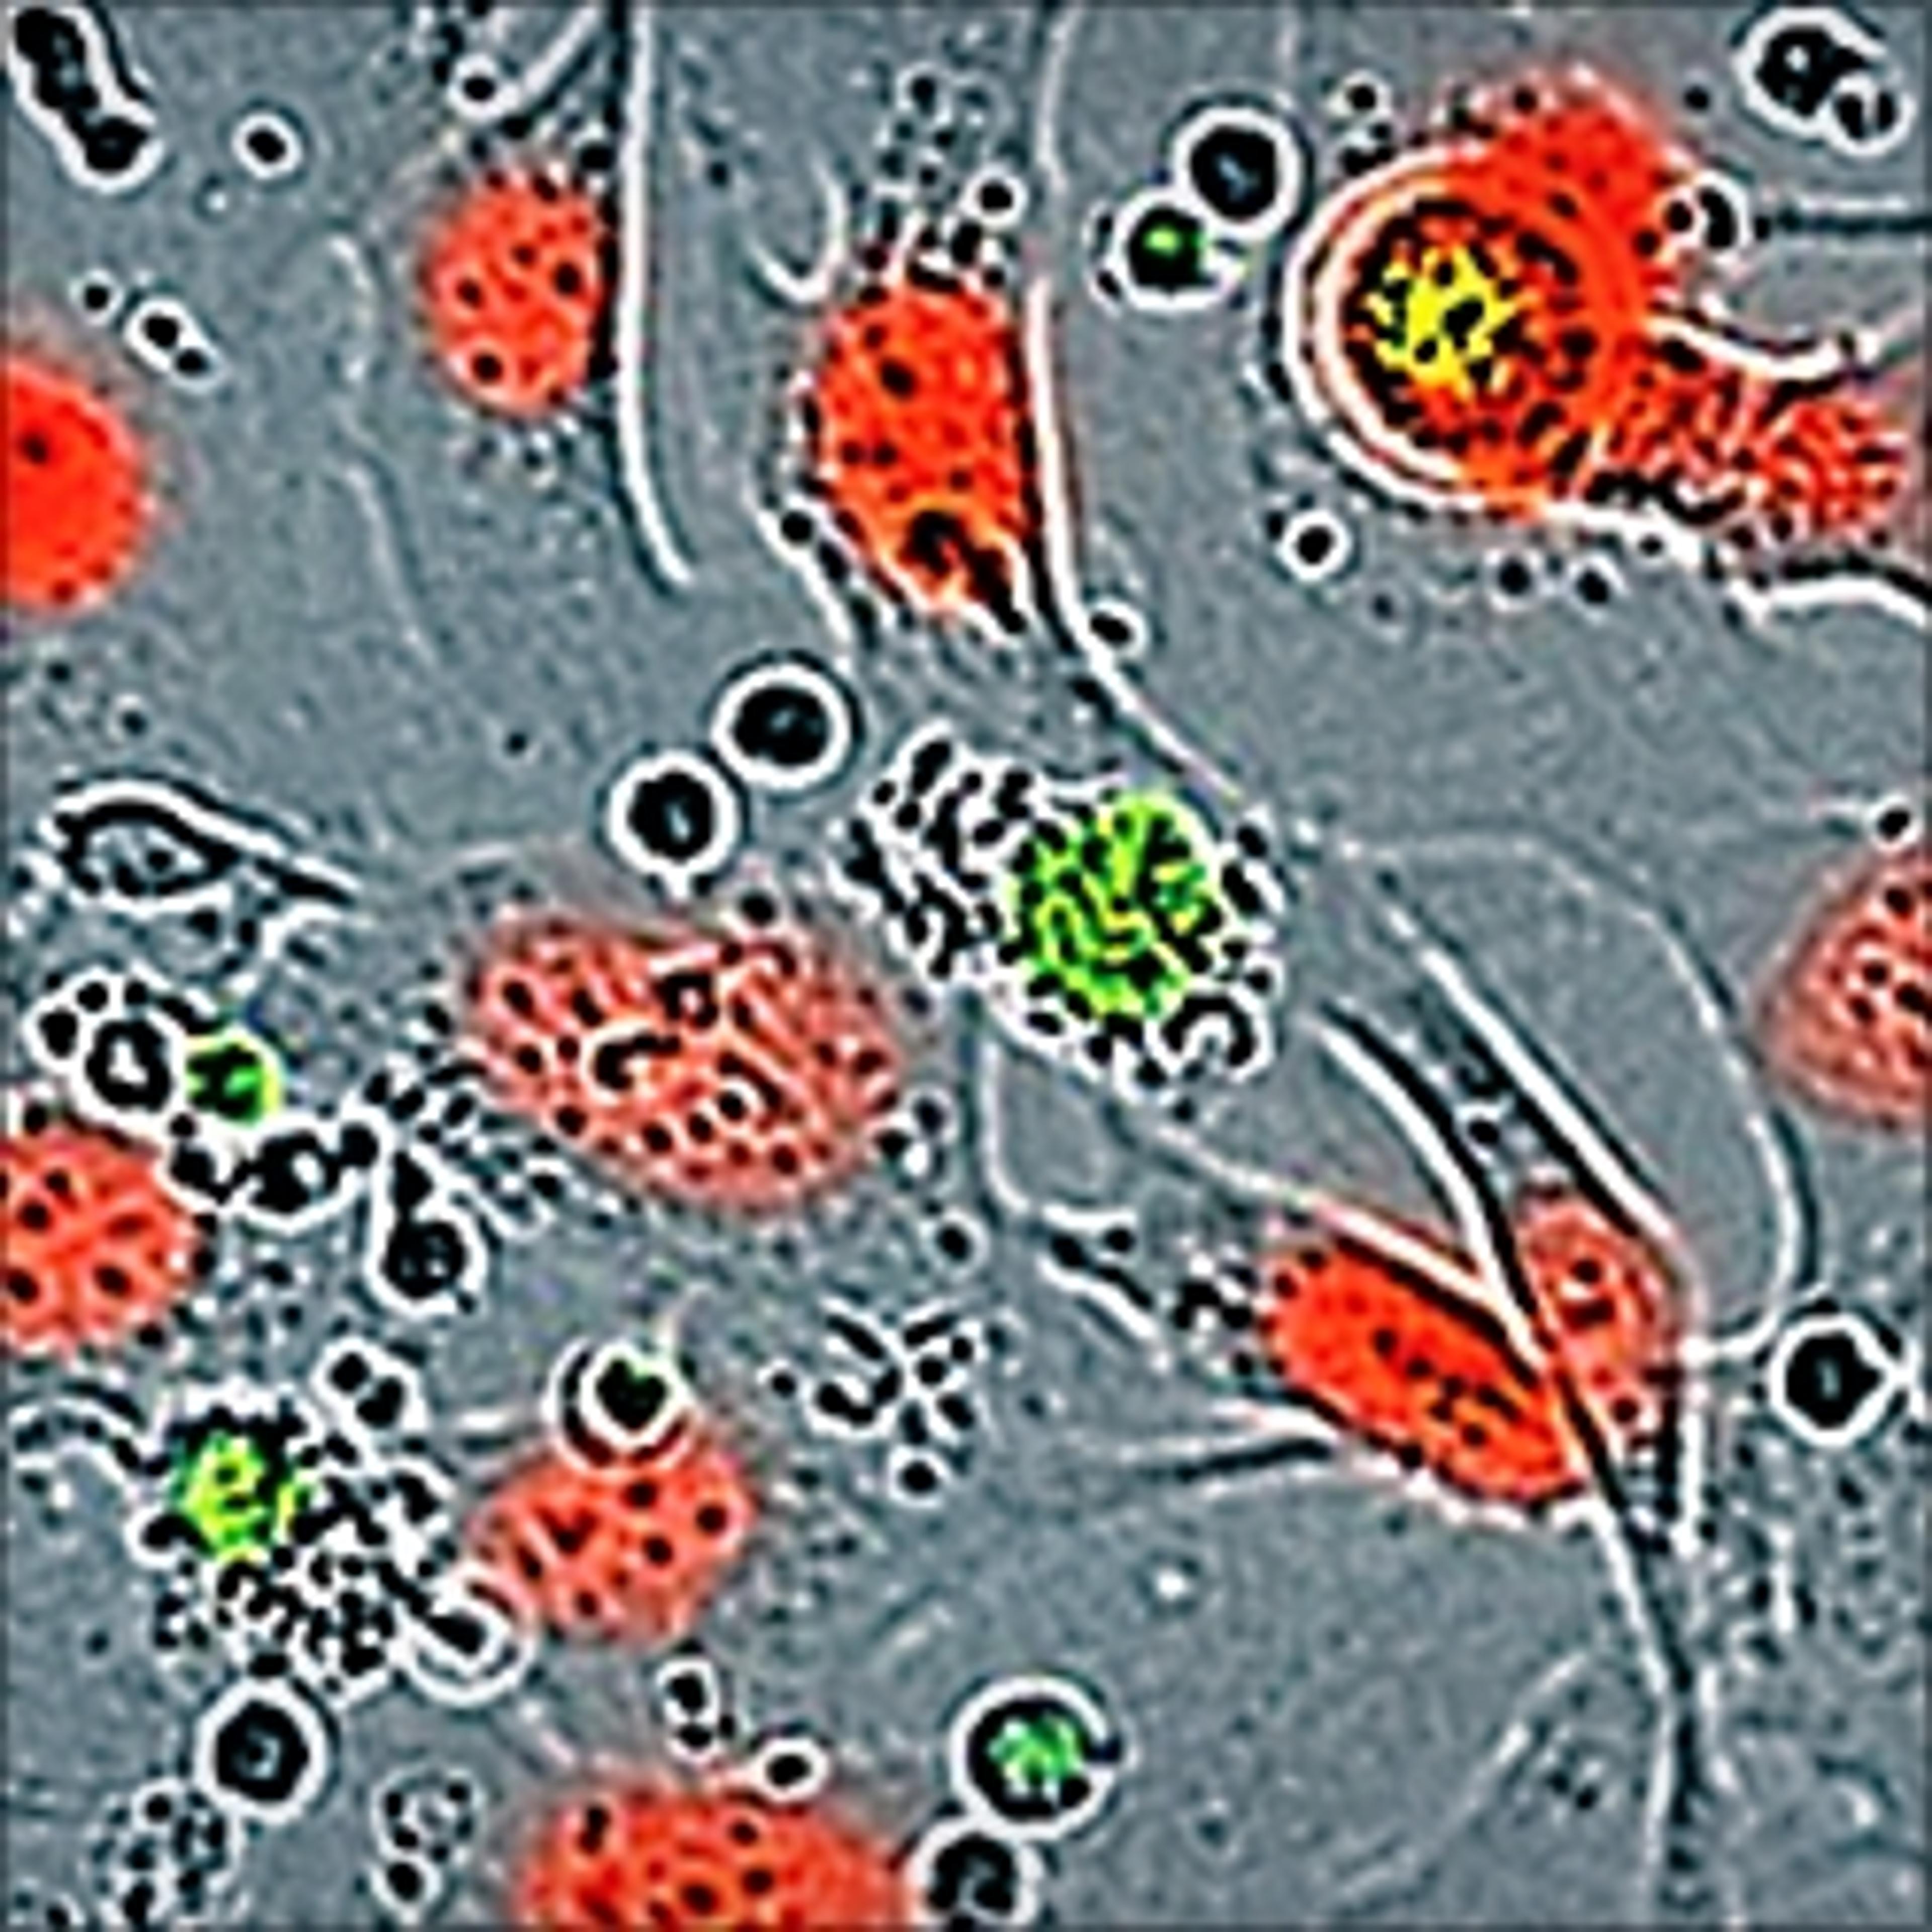

Analyze antibody or homing peptide-therapeutic agent internalization

The product is very effective for studying the internalization of complexes and also allows you to get highly reproducible results It is easy to use and has a convenient after-sale care. The cost of money is acceptable compared to the achievements obtained.

- Immune response – Immune cell killing

- Antibody Internalization

- Phagocytosis

- Cell-by-Cell Analysis